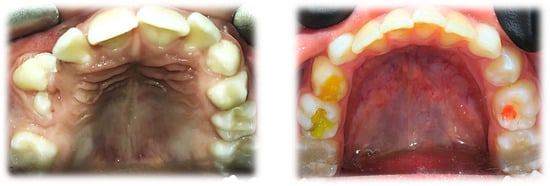

A functional assessment of the masticatory system did not reveal any kinematic jaw alteration. The movements of the mandible were symmetric, and their range was normal. Intraorally, mixed dentition was present with increased overjet and bilateral ½ cusp angle class II malocclusion. The oral vestibulum, in the area of the upper right primary canine (53) and first molar (54), was deformed due to alveolar bone expansion, and the overlying mucosa was red and swollen (Figure 2). The patient was referred for a radiological examination, as well as for a consultation at the Department of Oral Surgery.

Figure 2.

Intraoral photographs before treatment.

The initial orthodontic treatment plan required modification. Primarily, it was assumed that the traction of 13 would be required. This meant the need for the surgical exposure of the 13 crown, bonding of the attachment to the enamel surface and the application of an orthodontic fixed appliance in the upper dental arch. However, regular observations of 13 movement led to anticipating a spontaneous eruption on the condition that it would not be hindered by the malposition of Teeth 14 and 15. For this reason, the surgical exposure was unfounded. The aim of further orthodontic procedures was a distal movement of 14 and 15, to release the 13 eruption path. This was performed by an initial alignment with the aid of a specially designed transpalatal arch. On the right side, palatally from the first molar, an additional loop and a hook were added to a wire to enable the attachment of the elastic chain and provide a force to derotate the upper right second premolar (Figure 12). Subsequently, an attempt of derotation and alignment of the upper right first premolar was undertaken. However, due to the severe vestibuloposiotion of 14 and unfavorable alveolar boundary conditions, cautious orthodontic mechanics were required. Informed consent was obtained with notification of a possible revision in the treatment plan in case of a necessity to extract 14. The next step was a preadjusted fixed appliance therapy (MBT prescription, slot 0.022″) starting with a light continuous NiTi wire and continuing with a typical wire sequence and sliding mechanics (Figure 13).

Figure 12.

Upper occlusal photograph 9 months after surgery (a) and during orthodontic treatment (b).